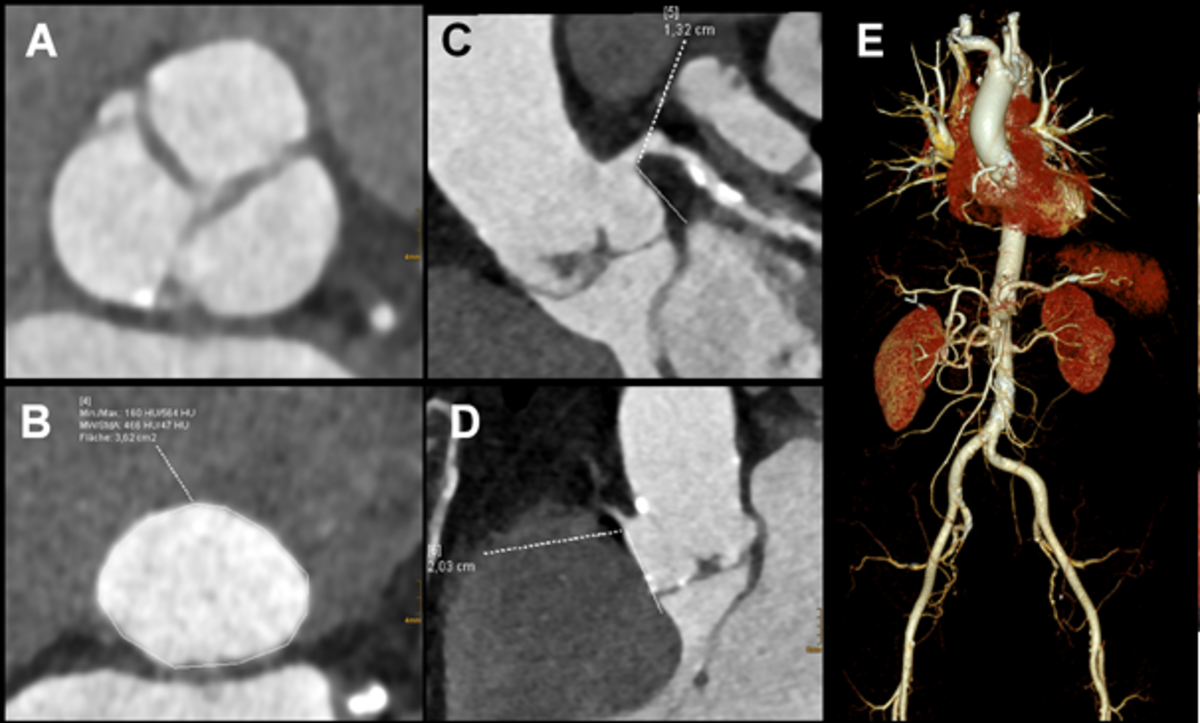

4) Planungsuntersuchungen vor Trans-Katheter Aortenklappenersatz (TAVI):

Patientinnen und Patienten mit hochgradiger Aortenklappenstenose erhalten heutzutage häufig einen sog. Trans-Katheter Aortenklappenersatz (TAVI). Zur Planung dieses Eingriffs und zur Auswahl der richtigen Klappengröße ist davor eine CT-Angiographie von Thorax und Abdomen erforderlich. Diese ermöglicht die genaue Charakterisierung der Aortenklappenanatomie (A) sowie der Größe des Aortenrings (B) sowie eine Abstandsbestimmung des Koronararterien-Ursprungs der linken (C) und rechten Koronararterie (D) von der Klappenebene. Gleichzeitig können auch die gesamte Aorta und die Beckenarterien beurteilt werden hinsichtlich der Eignung für einen Zugangsweg über die Leiste (E).